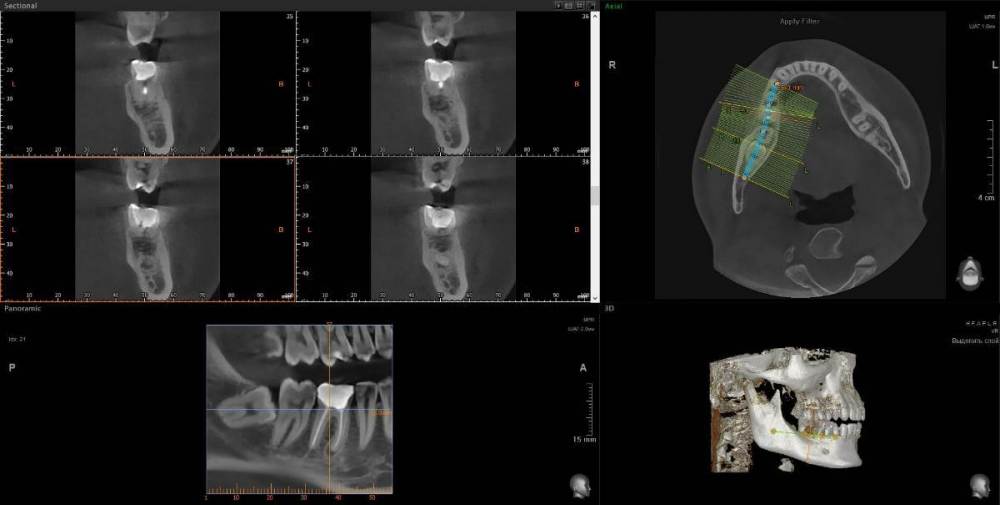

wladdX Опубликовано 17 января, 2024 Поделиться Опубликовано 17 января, 2024 (изменено) Думаю, что удаление зуба 46 - правильный выбор. Также имеется ретинированный зуб мудрости (48). С ним тоже лучше расстаться. У зуба 46 довольно широкая межкорневая перегородка, что даёт неплохие шансы на одномоментную установку имплантата. Зубы 18 и 28 (верхние зубы мудрости) наклонены щёчно, имеются кариозные полости недоступные для лечения - также на удаление Изменено 17 января, 2024 пользователем wladdX 2 Ссылка на комментарий

wladdX Опубликовано 17 января, 2024 Поделиться Опубликовано 17 января, 2024 Пора протезировать слева внизу 1 1 Ссылка на комментарий